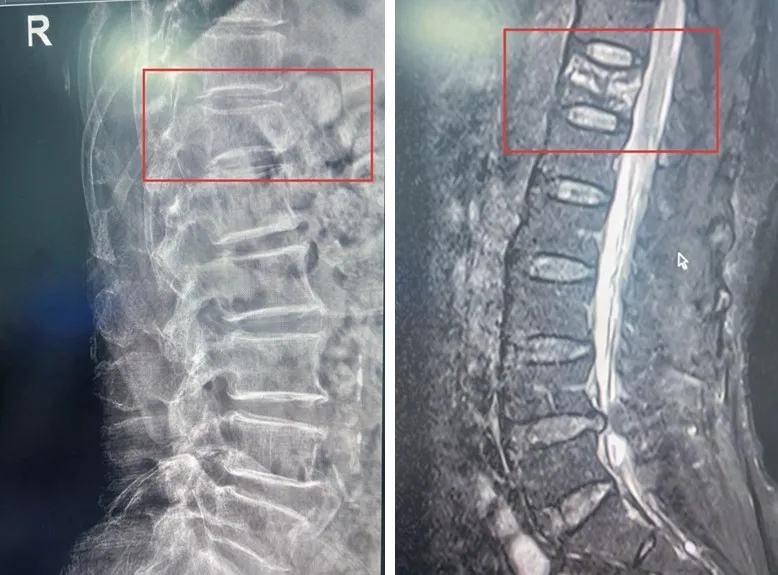

急诊科接诊后,立即为患者安排了放射线检查。影像结果显示,患者胸12椎体出现“楔形变”——就像一块砖头被压扁了一角,这是椎体压缩骨折的典型表现。

为进一步明确骨折性质和治疗方案,急诊科迅速邀请骨科医师张强会诊。张强评估后,当机立断建议:“立即加做胸椎磁共振检查!”这项检查如同给脊柱做了个“高清动态扫描”,能清晰分辨骨折是“新鲜的”还是“陈旧的”。结果很快出炉——新鲜胸12椎体压缩性骨折。这意味着骨折刚刚发生,正是进行微创干预的最佳时机。